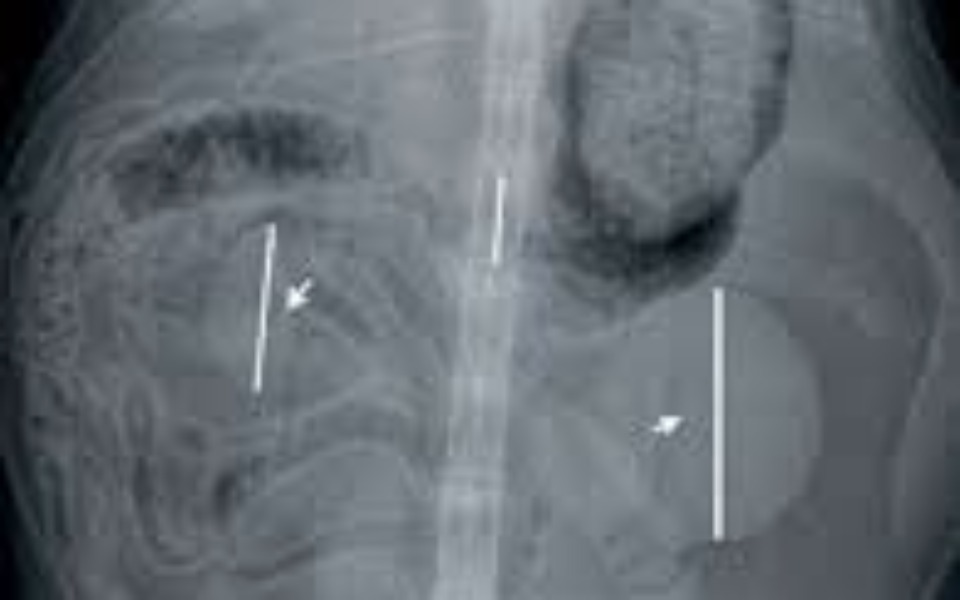

Witacie kochani mam na imię Zuma urodziłam sie w Maju 2023 roku i mam rok i 8 miesięcy Jestem amstaffem i z moimi wlascielami jestem od lipca 2023 roku . Bardzo ich kocham oraz kocham chodzić z nimi ma spacery . Wszyscy się mnie boją a prawda jest taka że nie potrafię skrzywdzić muchy . Niestety ostatnio zaczęłam bardzo chorować i lekarz stwierdził u mnie niestety wrodzoną wadę serca a dokładnie to zweżenie zastawki płucnej oraz moje jedna nerka jest większa od drugiej co zagraża mojemu zyciu i wiąże się z kosztownym leczeniem , na które niestety nie stać do końca moich właścicieli którzy robią wszystko co się da abym wróciła do pełnej aktywności . Bardzo chce wrócić do pełnej aktywności i proszę ludzi dobrego serca o pomoc w moim leczeniu i odzyskaniu pełnej sprawności. Pieniążki że zbiórki zostaną przekazane na moje dalsze leczenie oraz leki które pomogą mi wrócić do zdrowia .